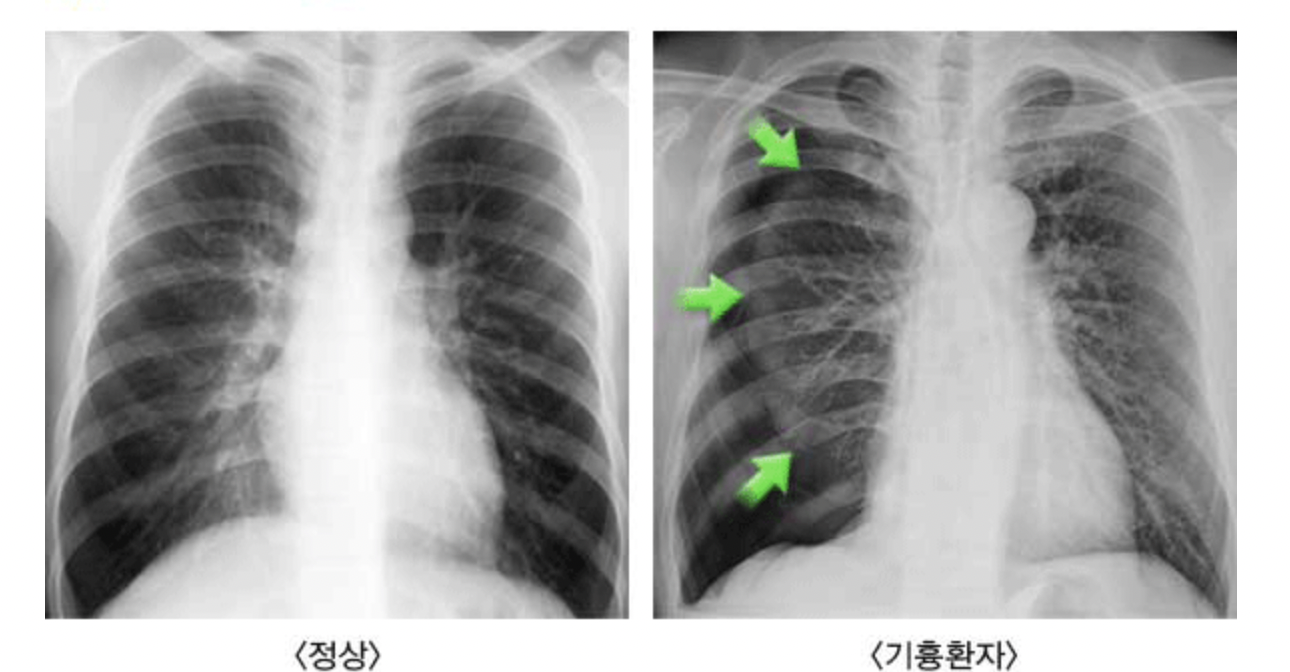

기흉의 진단을 위해서는 진찰을 통해 임상증상으로 진단하며 흉부 방사선 촬영(X-ray)을 통해 확진한다. 특히 기흉 환자의 40~50%에서 재발하는 양상을 보여 기흉의 과거력 청취도 중요한 요소가 된다. 흉부 방사선 촬영(X-ray)을 통해 폐의 모양 (찌그러진 양상) 및 흉강 안의 공기가 차 있는 상태를 확인한다. 특히 치료에 필요한 쇄골하 정맥 카테터 시술 등을 시행했을 경우 흉부 방사선 촬영을 시행하여 기흉 발생 여부를 미리 사정하는 것이 필요하다. 필요시 CT 검사를 시행하기도 한다.